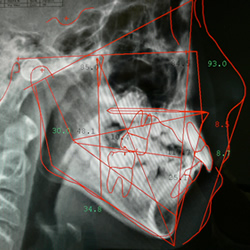

矯正治療はむし歯の治療などとは違い、すべての歯を移動させて咬み合わせを整える治療を行います。また、歯の移動だけでなく、顔やアゴの骨格の問題なども改善する必要があるため、治療を始める前に必ず精密検査が必要になります。

検査の結果を分析して、治療計画を説明することを診断といいますが、その方の不正咬合の状態によって、どのタイミングで治療を開始するのがいいのか、どのような治療方法がベストなのかは検査・診断を行わないと正確にはわからない場合があります。